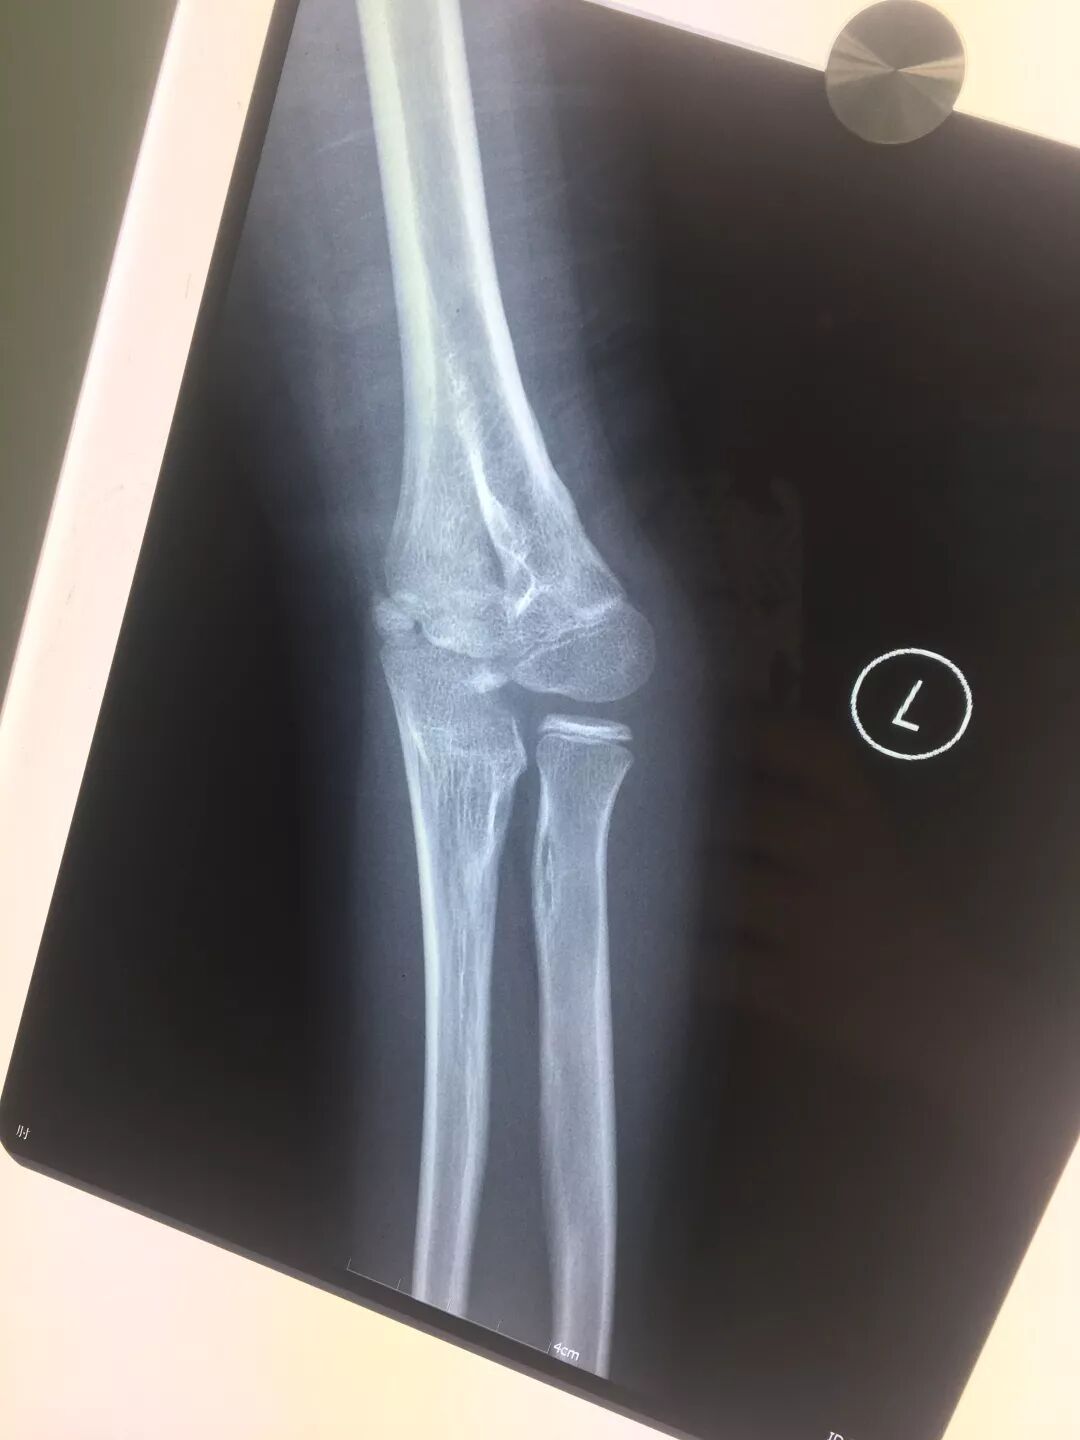

胳膊肘的正常片子图

胳膊肘的正常片子图,正常右胳膊拍片子图片

x线高清图谱|精致肘关节解剖

7种肘部损伤x片详细图解

正常的肘关节x光图